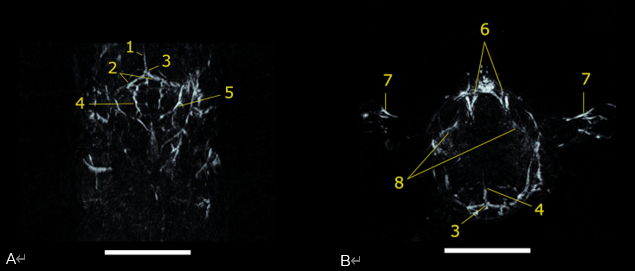

10 毫米厚的 (A) 冠狀和 (B) 橫向最大強(qiáng)度投影板,從 750 nm 掃描重建 PAI 體積。1) 上矢狀竇,2) 橫竇,3) 竇匯合處,4) 腦動脈,5) 耳動脈,6) 頸靜脈,7) 肱動脈,8) 眼動脈。比例尺為 5 毫米。